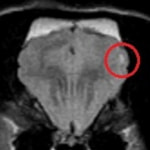

症例:キャバリア 6歳 未避妊メス

頻回の発作と後肢の起立不能を主訴に来院されました。MRI検査の結果、小脳左側にてT1強調画像で低信号、T2強調画像で高信号、FLAIR画像にて高信号、ガドリニウム造影剤にて軽度に増強される瀰漫性病変が認められました。また、大脳の全体的な腫大、軽度のキアリ様奇形、左側の鼓室胞炎が認められました。小脳梗塞もしくはGME、およびキアリ様奇形、鼓室胞炎と診断し、抗てんかん薬、グルココルチコイド、抗生剤、ビタミン剤による内科療法を開始しました。初発発作から3ヵ月後のfollow up MRIでは小脳病変の顕著な改善が認められ、現在は抗てんかん薬のみで良好な経過をたどっています。

T1強調画像

T1強調画像(造影)

T2強調画像

FLAIR画像